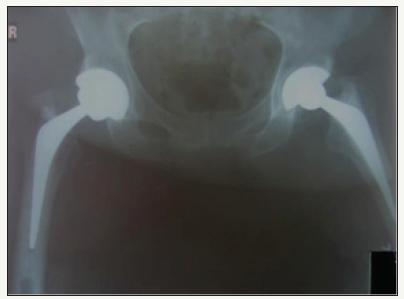

A 70 year old male underwent right total hip arthroplasty for osteoarthritis (Figure 6). A 56mm Pinnacle sector 2 acetabular cup was inserted with a neutral Marathon polyethylene liner (28mm ID x 56mm OD) and mated via a 28mm+5 high offset stainless steel Articul/Eze femoral head (12/14 cone) to an uncemented No 11 Corail stem. Post-op recovery was uneventful. Post-op X-Rays showed 46° of inclination of the cup (Figure 7).

figure 6: Pre-op AP film showing right hip osteoarthritis.

figure 7: Post-op right total hip arthroplasty.

figure 8: Right hip liner disassociation.

At six week follow-up he was noted to have a slight Trendelenburg gait but was otherwise well with no reports of instability. At 19 months post-op he presented acutely after bending forwards flexing at his hip and feeling something “pop” within his hip. He was able to mobilise soon after although with some difficulty and reported feeling something “rubbing” within the hip. Again, X-Rays showed an eccentrically placed femoral head (Figure 8 & 9).

figure 9: Lateral film showing liner disassociation.

figure 10: Post-revision film.

He underwent revision surgery where again it was found that the three consecutive superiorly placed locking tabs had sheared off resulting in the liner dissociating. Again cup and femoral anteversion were deemed acceptable and there was no evidence of loosening and both were therefore retained. The disassociated liner was replaced with a neutral metal Pinnacle liner (36mm IDx56mm OD) and the femoral head component with a 36mm +5 offset stainless steel Articul/Eze head (12/14 taper). Post-operative recovery was uneventful and on review in outpatient clinic 6 weeks post-op and at one year he was mobilising well with full range of movement of the hip and reported no further episodes of instability (Figure 10).